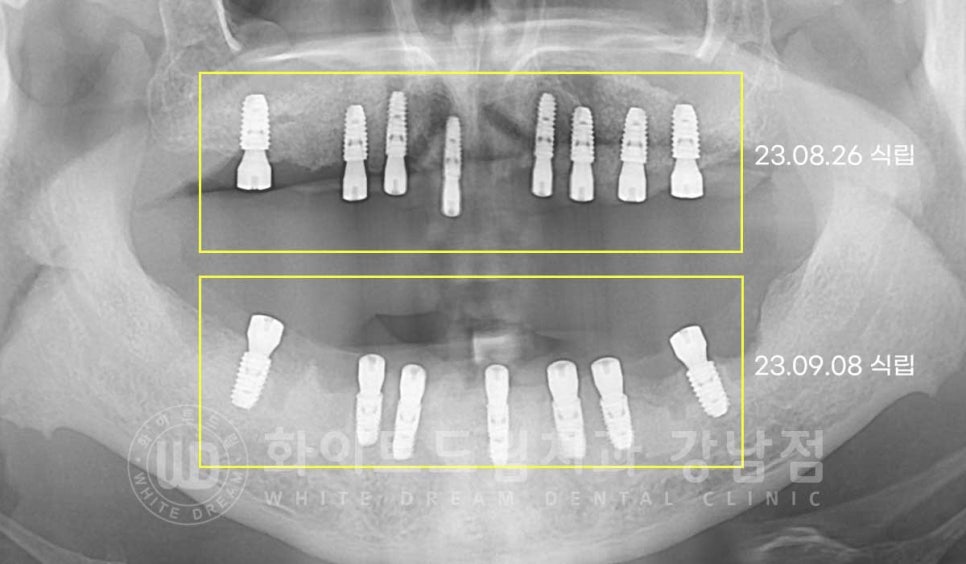

임플란트 재수술 잘하는치과

▲ 당일 2차 수술까지 모두 완료한 수술 후 구내 상태.

다행히 환자분은 임플란트 재수술 부위 외에는

잇몸뼈에 심한 염증이 있는 상태가 아니었습니다.

초기 임플란트 고정력이 안정적이게 확보가 되는 상황이어서

내원 횟수를 줄이고, 치료 과정을 단축시킬 수 있도록

2차 수술까지 당일 모두 진행을 했습니다.

총 5개월의 치료 기간으로 모든 치료가 완료되었습니다.

기간 : 23.08.26 - 24.02.03

1, 2차 수술을 동시 진행하여 치료 기간을 단축시킨 것도 있지만

원내 기공실에서 원장님과 상의하며 빠르게 보철 제작이 가능하기에

멀리서 내원을 하시는 경우에도 이렇게 빠른 임플란트 치료를 받아보실 수 있답니다.